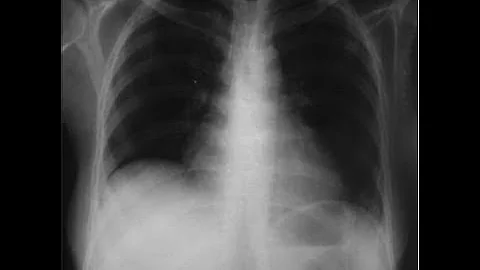

About 50% of people with lupus will experience lung involvement at some point - are you prepared to recognize the signs?